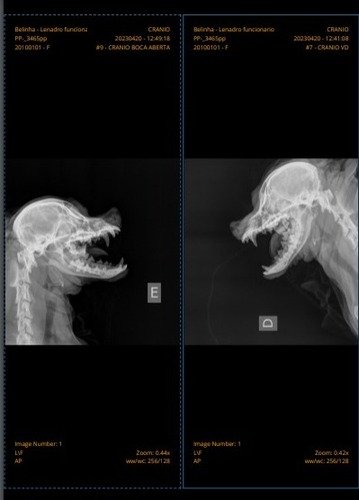

Fui ao médico, mas eles não conseguiram me diagnosticar. Estive internada por 4 dias seguidos, tive gastos com Raio X (pra ver se eu não tinha quebrado a mandíbula) e medicamentos.

Minha mamãe não tem mais dinheiro pra pagar meus exames e remédios. Meus remédios juntos dão mais de R$200 e o Raio X deu R$210. Os veterinários estão com algumas suspeitas, então estou tomando diversos remédios para amenizar os sintomas. Além disso, só consigo comer comidas pastosas, já que a minha boca não fecha mais.